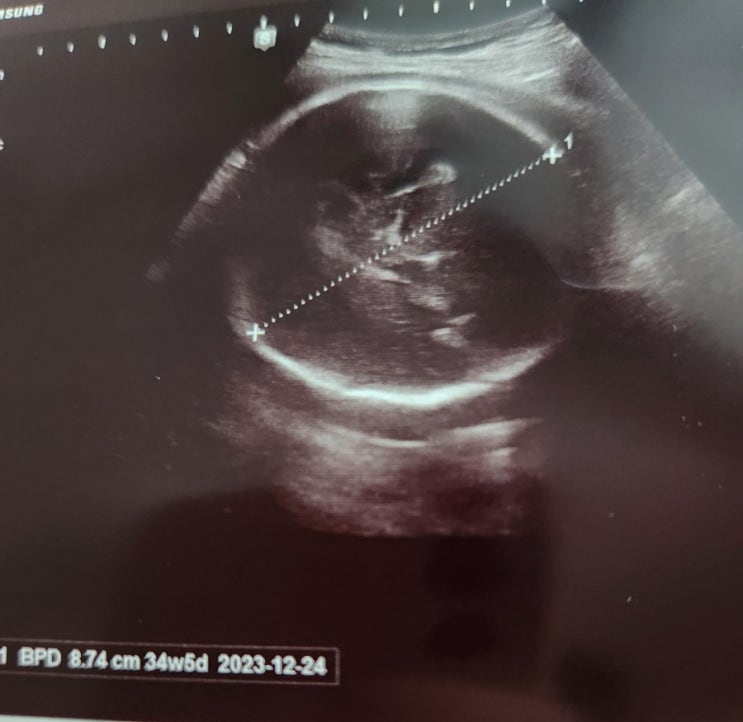

둘째임신, 35주+3일 태아몸무게 2kg 작은아이 키우기 태아성장지연??

35주 3일 태아몸무게 1956g 머리 34+5 배 31+0 다리 32+1 주수보다 1~2주 작았으나 큰 문제 없다고해서 늘 ...